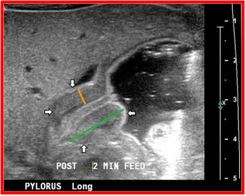

诊 断

◇临床表现:典型的呕吐,右上腹扪及肿块即可确诊

◇B超:肌层厚度≥0.4cm,SD=厚度×2/直径≥50%

◇如未扪及肿块,B超指数不肯定,可行GI检查: